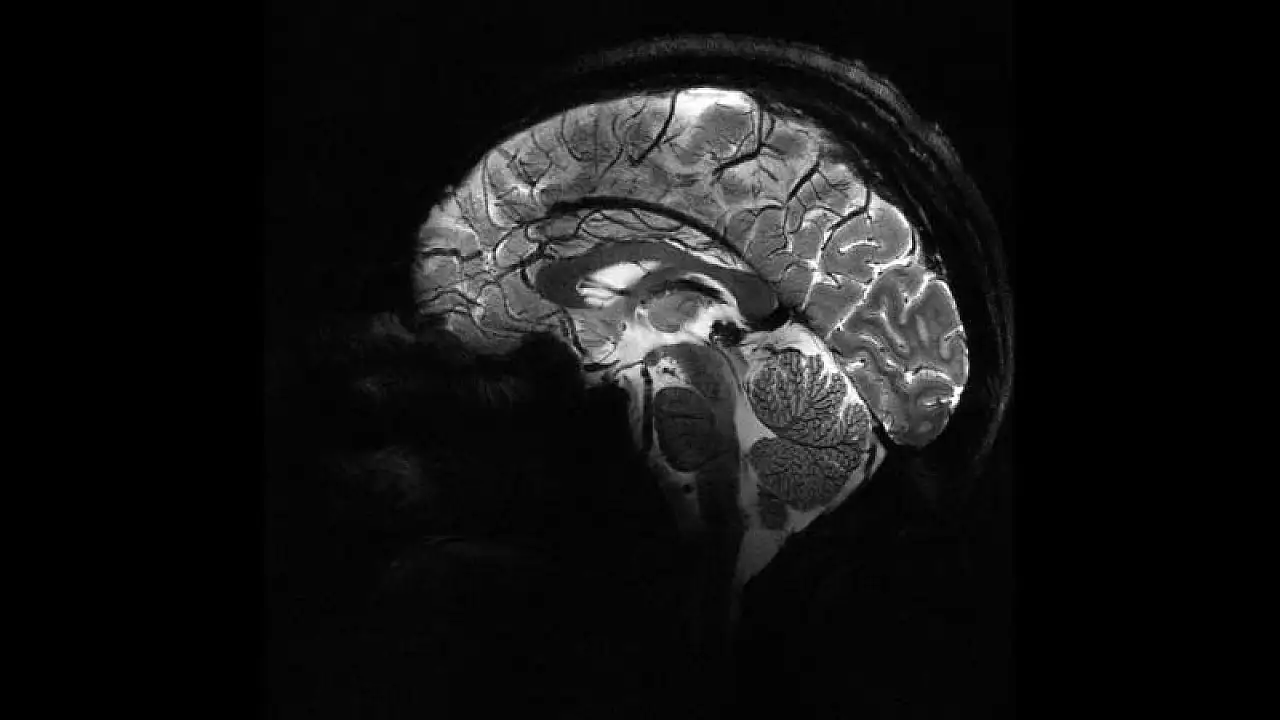

Aşırı sıcaklar beyin kanaması riskini artırıyor

SICAK HAVA BEYİN SAĞLIĞINI TEHDİT EDİYOR

Artan sıcaklıkların, vücuttaki sıvı ve elektrolit dengesini bozduğunu, derideki damarların aşırı genişlemesine ve fazla terlemeye bağlı olarak kan dolaşımının olumsuz etkilendiğini belirten Dr. Kaplan, bu durumun beynin yeterince kan ve oksijen alamamasına yol açabildiğini ifade etti.

Özellikle nem oranının yüksek olduğu zamanlarda, terlemenin azalmasıyla birlikte vücut ısısının tehlikeli seviyelere ulaşabileceğini kaydeden Kaplan, bu gibi durumlarda şuur kaybı, epilepsi (sara) nöbeti, beyin kanaması, anevrizma patlaması ve hatta beyin damarlarında tıkanmaların görülebileceğine dikkat çekti.